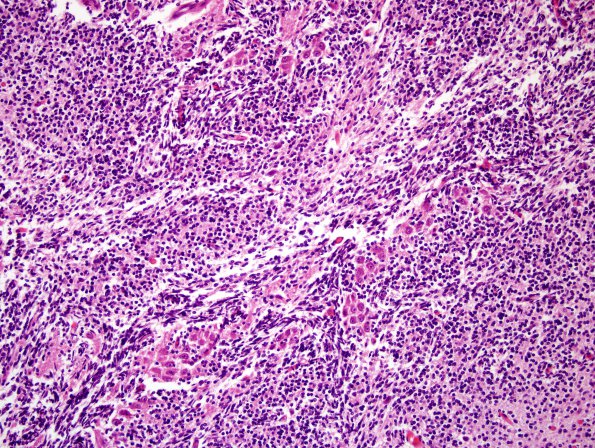

Area of arrows in image 10A1 shows dense collections of immature granule cells (H&E)